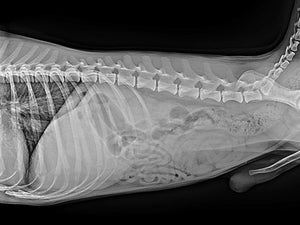

The Veterinary LG Digital X‑ray Detector is engineered for portability, durability, and high‑precision imaging across a wide range of veterinary applications. Designed with a rear‑sided handle, sculpted handgrips, and chamfered edges, it is easy to carry, position, and manoeuvre in fast‑paced clinical environments. With up to 8 hours of operating life and Hot Swap removable batteries, the detector maintains power for up to one minute during battery changes, ensuring a seamless workflow with no interruptions.

For superior diagnostic clarity, the system can be paired with a 27" 8MP IPS clinical review monitor, delivering exceptionally sharp, detailed images for confident interpretation.

Pixel size 140 μm for high‑resolution imaging

16‑bit A/D conversion for superior contrast detail

Scintillator: CsI for high sensitivity and low noise